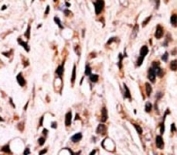

IHC analysis of FFPE breast carcinoma stained with phospho-SMAD4 antibody.